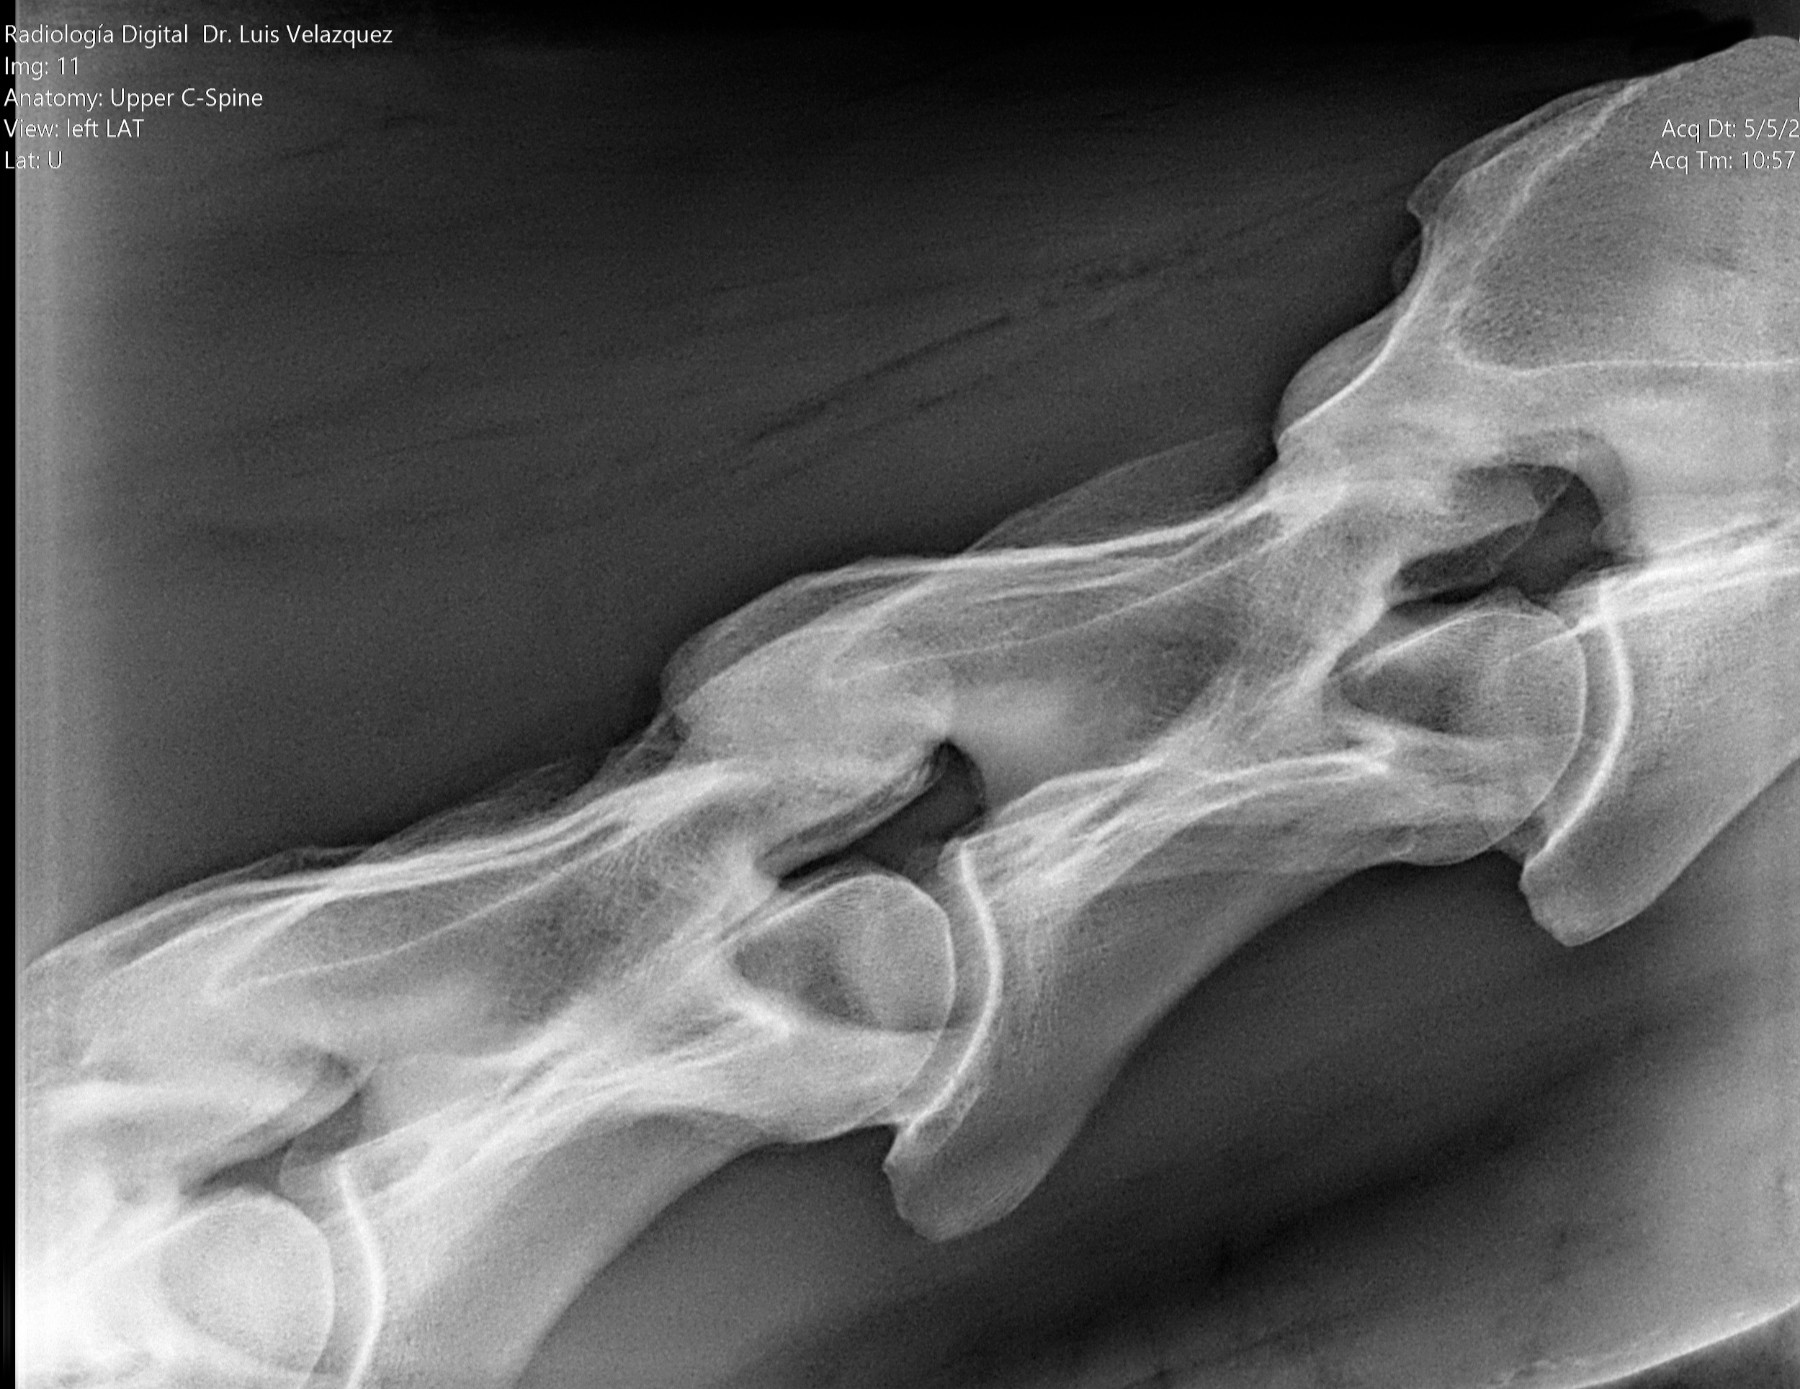

Radiología Digital como Herramienta Complementaria en el Dictamen de Bienes Muebles

Desde el descubrimiento de los rayos “X” y las placas radiográficas por Wilhelm Conrad Roentgen y su posterior difusión a través de la Asociación Físico médica de Wurzburg el 28 de diciembre de 1895, que fue la primera asociación que habló de los nuevos rayos que podían penetrar el cuerpo y fotografiar los huesos, ha habido muchos cambios tanto en la forma de obtener, procesar e incluso en la forma de visualizar, manejar y almacenar las placas radiográficas.